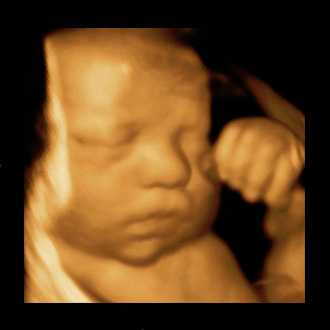

3D/4D SONOGRAPHY

3D/4D SONOGRAPHY (Live)

Built on a digital platform, the Voluson 730 utilizes advanced signal processing technology to ensure optimal image quality for high-resolution 2D, volumetric 3D and real-time 4D imaging. Image quality is further enhanced with Harmonic imaging, spectral, color and Doppler imaging,as well as our latest advance – Compound Resolution Imaging.

• High-resolution 2D, volumetric 3D and real-time 4D imaging